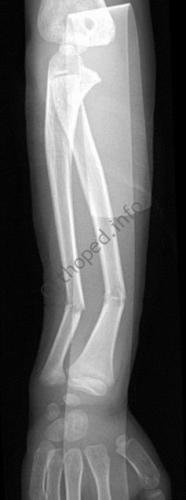

Fracture de l’avant-bras 31 mars 202519 mars 2024 par Damien Traitement Traitement orthopédique Embrochage centro-médullaire